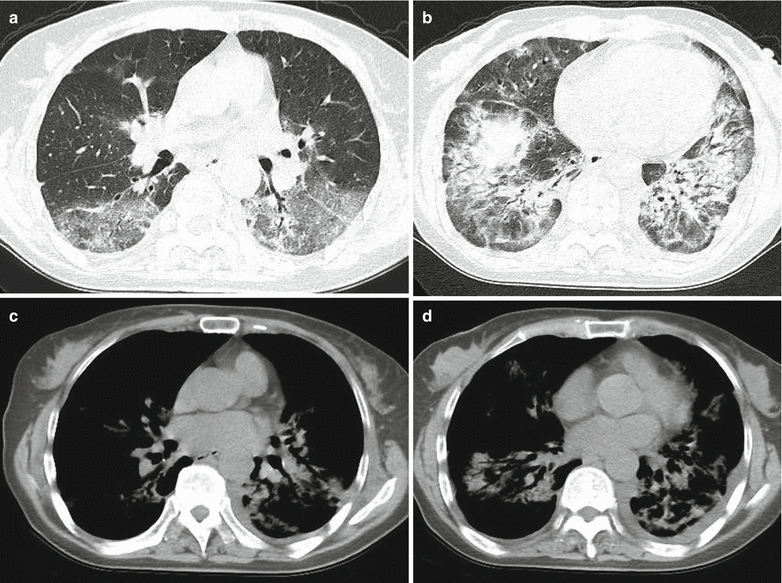

From journals.lww.com

Computed Tomographic Features of Legionella pneumophila Pneu How Common Is Legionella Pneumonia While there are at least 60 species of legionella, legionnaires’ disease is most often caused by legionella pneumophila. A fact sheet that provides general information about legionnaires' disease. Legionella is a relatively common cause of community acquired pneumonia (cap). It's caused by a bacterium. In published series analysing causative pathogens of cap,. The fact sheet describes symptoms and. Legionnaires' disease. How Common Is Legionella Pneumonia.

Legionella Pneumonia Ct Scan How Common Is Legionella Pneumonia You get legionnaires’ disease when legionella infects your lungs. In published series analysing causative pathogens of cap,. Legionnaires' disease is a serious type of pneumonia caused by legionella bacteria. Legionnaires' disease is a lung infection you can get from inhaling droplets of water from things like air conditioning or hot tubs. For patients with pneumonia, the following indications warrant testing. How Common Is Legionella Pneumonia.